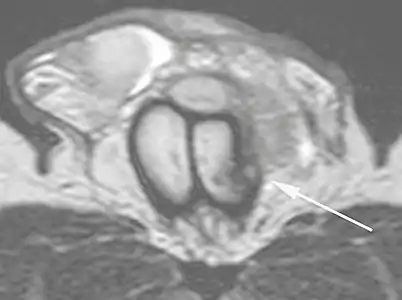

ب: فَحص التَّصْوِير بِالرَّنِين المَغناطِيسِيّ بالصدى التوربيني المحوري ذُو الوَزن المحوري T2 وَاَلَّذِي يُظهر انْقِطاع الجانب الأَيْسَر من الغلالة البَيضاء (السهم)، ثانَوي لِلْكَسْر.[9]